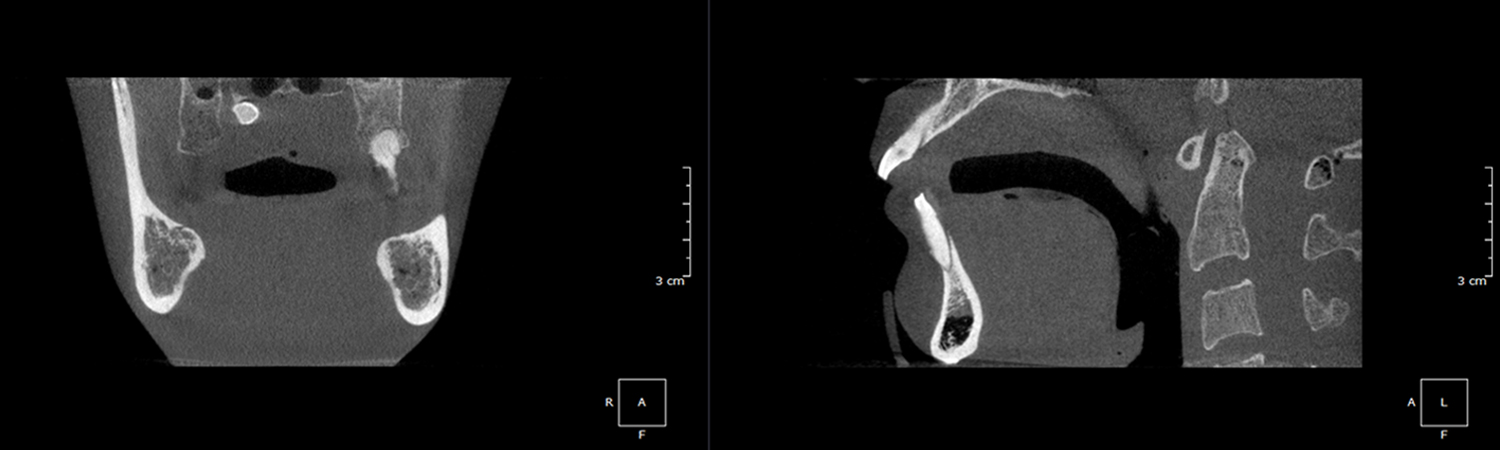

Undistorted, anatomically correct views of the jaws, teeth and facial bones along with cross-sectional (bucco-lingual), axial, coronal, sagittal, cephalometric and panoramic views are easily generated.